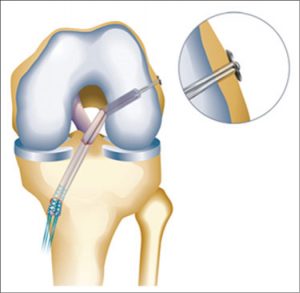

Schema van bottunnels bij kruisbandreconstructie

Tijdens de kijkoperatie worden de oude resten van de gescheurde kruisband verwijderd. Er worden 2 tunnels geboord, één in scheenbeen en één in dijbeen. Beide tunnels worden gepositioneerd op de plaats van de oorspronkelijke kruisband. In uitzonderlijke gevallen kan gewerkt worden met meerdere tunnels (double bundle techniek).

Het geheel wordt via de boortunnels in de knie gebracht.

De nieuwe pees wordt opgehangen in de tunnel van het dijbeen. Klassiek wordt een endobutton systeem gebruikt.

Nadien gebeurt de fixatie op de juiste spanning op het scheenbeen.